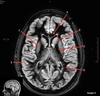

Image weighting and axis

T2 Axial

A

Caudate Nucleus

B

Thalamus

C

Third ventricle

D

Lentiform Nucleus

E

Frontal Sinus

Basal Ganglia

Posterior horn lateral ventricle